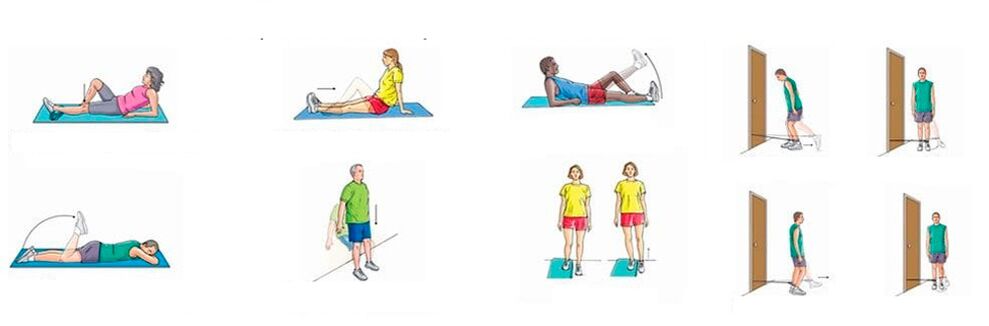

Bei chronischen Schmerzen in den Kniegelenken, wenn keine nennenswerte Entzündung vorliegt, können Sie körperliche Übungen durchführen, die das Muskel-Band-System stärken, die Durchblutung und den Stoffwechsel verbessern. Durch systematisches Training lassen die Schmerzen allmählich nach, obwohl die Beine ziemlich knackig sind.

Eine ungefähre Reihe von Übungen gegen Knieschmerzen:

- Festes Knie. Legen Sie sich auf den Rücken, beugen Sie ein Bein am Knie, heben Sie es an und halten Sie es eine Minute lang in diesem Zustand. das zweite Bein ist zu diesem Zeitpunkt bewegungslos; Strecken Sie Ihr Bein sehr langsam und senken Sie es ab, ruhen Sie sich 10 Sekunden lang aus und wiederholen Sie die Übung mit dem anderen Bein. 10 Mal wiederholen;

- Doppeltes Beugen der Beine mit den Knien nahe am Gesicht. Legen Sie sich auf den Rücken, beugen Sie die Beine an den Hüften und Knien, fixieren Sie letztere in der Nähe Ihres Gesichts und halten Sie sie eine Minute lang so. Dann strecken und senken Sie langsam Ihre Beine, ruhen Sie sich 10 Sekunden lang aus und wiederholen Sie den Vorgang. Machen Sie 5–6 Ansätze und erhöhen Sie die Belastung schrittweise.

Akute Schmerzen im Knie erfordern einen Ruhezustand; jegliche körperliche Aktivität und Training sind kontraindiziert.

Bei akuten Schmerzen im Kniegelenk, begleitet von Schwellungen und Rötungen der Haut, einer Verletzung des Allgemeinzustandes, Fieber, darf das Bein nicht bewegt werden, es muss in Ruhe gehalten werden. Und erst wenn die Entzündung nachlässt, können Sie zunächst zu passiven Übungen (durchgeführt von einem Assistenten) und dann zu aktiven Übungen (durchgeführt vom Patienten selbst) übergehen.